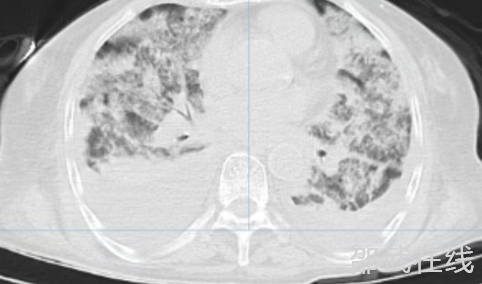

»¼ÕßËæ¼´×ªÈë¸ÐȾ¿ÆÇÀ¾È£¬¸µ±óºìÖ÷ÈÎÒ½Ê¦Ç£Í·ÖÆ¶¨¸öÌ廯ÖÎÁÆ·½°¸£¬¸øÓ迹¸ÐȾ¡¢Éýѹ¡¢ÊäѪС°å¡¢¾­±Ç¸ßÁ÷Á¿¸øÑõµÈ×ÛºÏÖÎÁÆ¡£È»¶ø²¡ÇéÈÔÒ»²¨ÈýÕÛ£ºÖÎÁÆ 2 Ììºó»¼ÕßÌåÎÂϽµ£¬µ«ÑªÑõ±¥ºÍ¶È³ÖÐøÔÚ 70-88% µÄΣÏÕÇø¼ä£¬¸´²éÐØ²¿ CT ÏÔʾ˫·ÎµûÒíÕ÷¡¢·ÎË®Ö׺ϲ¢ÐØÇ»»ýÒº£¬Ìáʾ ARDS ¼ÓÖØ¡£ÖØÖ¢Ò½Ñ§¿ÆÍŶӽô¼±½éÈ룬Ϊ»¼ÕßÊµÊ©Æø¹Ü²å¹ÜºÍÓд´»úÐµÍ¨Æø£¬²ÉÓ÷α£»¤ÐÔÍ¨Æø²ßÂԳɹ¦¾ÀÕýÍç¹ÌÐÔµÍÑõѪ֢£¬Öú»¼Õß´³¹ýºôÎüË¥½ßÄѹء£       ¾­¹ýϵÁÐÖÎÁÆ£¬»¼Õ߸÷ÏîÖ¸±êÖ𲽸ÄÉÆ£¬Ë³ÀûÍÑÀëºôÎü»ú£¬¼´½«¿µ¸´³öÔº¡£²»ÁϳöԺǰһÌ죬»¼ÕßÍ»·¢Ïû»¯µÀ´ó³öѪ£¬Ñªºìµ°°×´Ó 87g/L Öè½µÖÁ 51g/L£¬ÉúÃüÔÙ´ÎÊÜÍþв¡£Ò½Îñ²¿Ñ¸ËÙ×é֯賦Íâ¿Æ¡¢Ñª¹ÜÍâ¿Æ¡¢Ïû»¯ÄڿƵȶàѧ¿Æ£¨MDT£©»áÕ¾­»áÕï¼°¼±Õï賦¾µÊ±·¢ÏÖ»ØÃ¤²¿£¬ÓÐÉøÑª£¬×ۺϿ¼ÂdzöѪ²¿Î»ÔÚС³¦£¬Òòȱ·¦Ð¡³¦¾µ£¬ÎÞ·¨ÔÚÄÚ¾µÏÂÅжÏÊǾֲ¿»¹Êǹ㷺³öѪ£¬ÎÞ·¨ÔÚÄÚ¾µÏÂֹѪ£¬Ö»ÄܲÉÈ¡±£ÊØÖÎÁÆ£¬ÇÒ±£ÊØÖÎÁÆ·çÏÕ¼«´ó£¬ËæÊ±¿ÉÄܳöÏÖÏû»¯µÀ´ó³öѪ¡£µ¼ÖÂʧѪÐÔÐݿˡ¢ËÀÍöµÈ·çÏÕ£¬½¨ÒéתÉϼ¶Ò½ÔºÍêÉÆÐ¡³¦¾µ¡£µ«ÔÚ»¼Õß¼°¼ÒÊôµÄ¼á³ÖÏ£¬ÒªÇó¼ÌÐøÔÚÎÒÔº±£ÊØÖÎÁÆ£¬Ò½ÁÆÍŶӲÉÈ¡Êä×¢ 1200ml È¥°×Ðü¸¡ºìϸ°û¡¢Ö¹Ñª¡¢ÒÖÖÆÎ¸ËáµÈ±£ÊØÖÎÁÆ£¬5 Ììºó³öѪ³É¹¦¿ØÖÆ£¬»¼ÕßѪºìµ°°×Îȶ¨ÔÚ 103-108g/L¡£